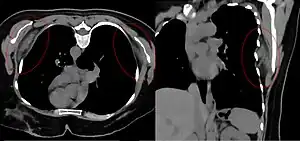

| Bilateral elastofibroma dorsi in native computed tomography: left image axial in prone position (for biopsy), right image oblique coronal view. | |

By computed tomography, there is a poorly circumscribed, heterogeneous soft tissue mass, with a signal intensity similar to skeletal muscle. The fact that the lesion may be bilateral, helps eliminate a sarcoma from further consideration.[6] At US, elastofibromas are depicted deep to the musculature as a multilayered pattern of hypoechoic linear areas of fat deposition intermixed with echogenic fibroelastic tissue.[7] The mass often protrudes from the subscapular region upon shoulder abduction, allowing better delineation of the finding.[8]